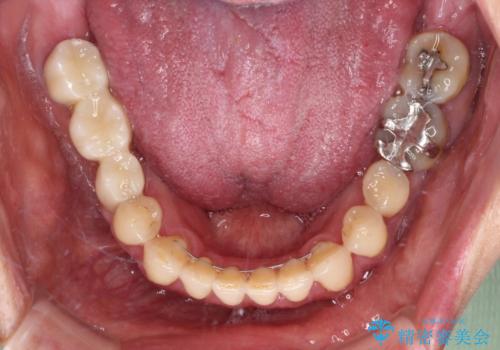

反対咬合や欠損を治療したい インビザライン矯正とオールセラミックブリッジ

- 虫歯治療がうまく進まないとのことで来院された患者様です。

虫歯治療や欠損補綴治療も必要でしたが、前歯が反対咬合であったので、セラミッククラウンやブリッジによる治療と並行して矯正治療を提案しました。

仕事柄海外出張が多いとのことで、虫歯治療後にインビザラインにて矯正治療を行うこととしました。